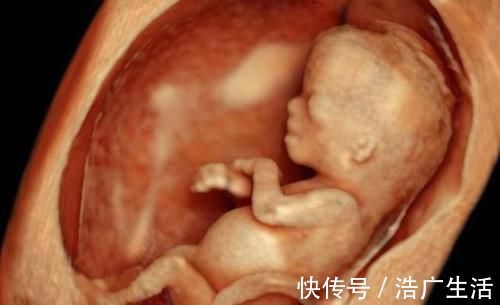

生过孩子的宝妈都知道孩子要在我们子宫里待够280天才会出来,而在这280天里胎宝宝都要待在宝妈那个既昏暗又拥挤的子宫里生活。

可能有的孕妈很惊讶,为什么子宫又混乱又拥挤,小宝宝就能在里面生活这么长时间,而且仅靠与母亲相连,接得一根脐带和胎盘,就能够吸取足够的营养和氧气真的是太神奇了。